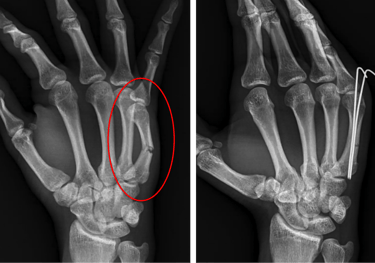

Hand & Wrist Fracture Management

Metacarpal & Phalangeal Fractures